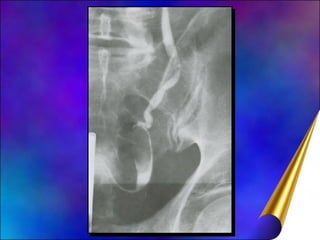

Neoplasia de Pelve Renal e de Ureter CPRs raros, 6% dos Tu renais; 3:1; 60-70 anos Relação tu rim, bacinete, ureter = 51:3:1 CPRs: fumo, analgésico (fenacetina), anilina I.U. crônica associada litíase renal (Câncer epidermóide pelve renal) Associação CPR a Tu bexiga é freqüente (30 a 75%)

Diagnóstico Hematúria Indolor, cólica renal (coágulos) Obstrução: dor surda e contínua Tu assintomático (descobertos acidentalmente) U.Excretora: defeito de enchimento bacinete, cálices

Neoplasia de PelveRenal e de Ureter CPRs raros, 6% dos Tu renais; 3:1; 60-70 anos Relação tu rim, bacinete, ureter = 51:3:1 CPRs: fumo, analgésico (fenacetina), anilina I.U. crônica associada litíase renal (Câncer epidermóide pelve renal) Associação CPR a Tu bexiga é freqüente (30 a 75%)

Diagnóstico Hematúria Indolor,cólica renal (coágulos) Obstrução: dor surda e contínua Tu assintomático (descobertos acidentalmente) U.Excretora: defeito de enchimento bacinete, cálices